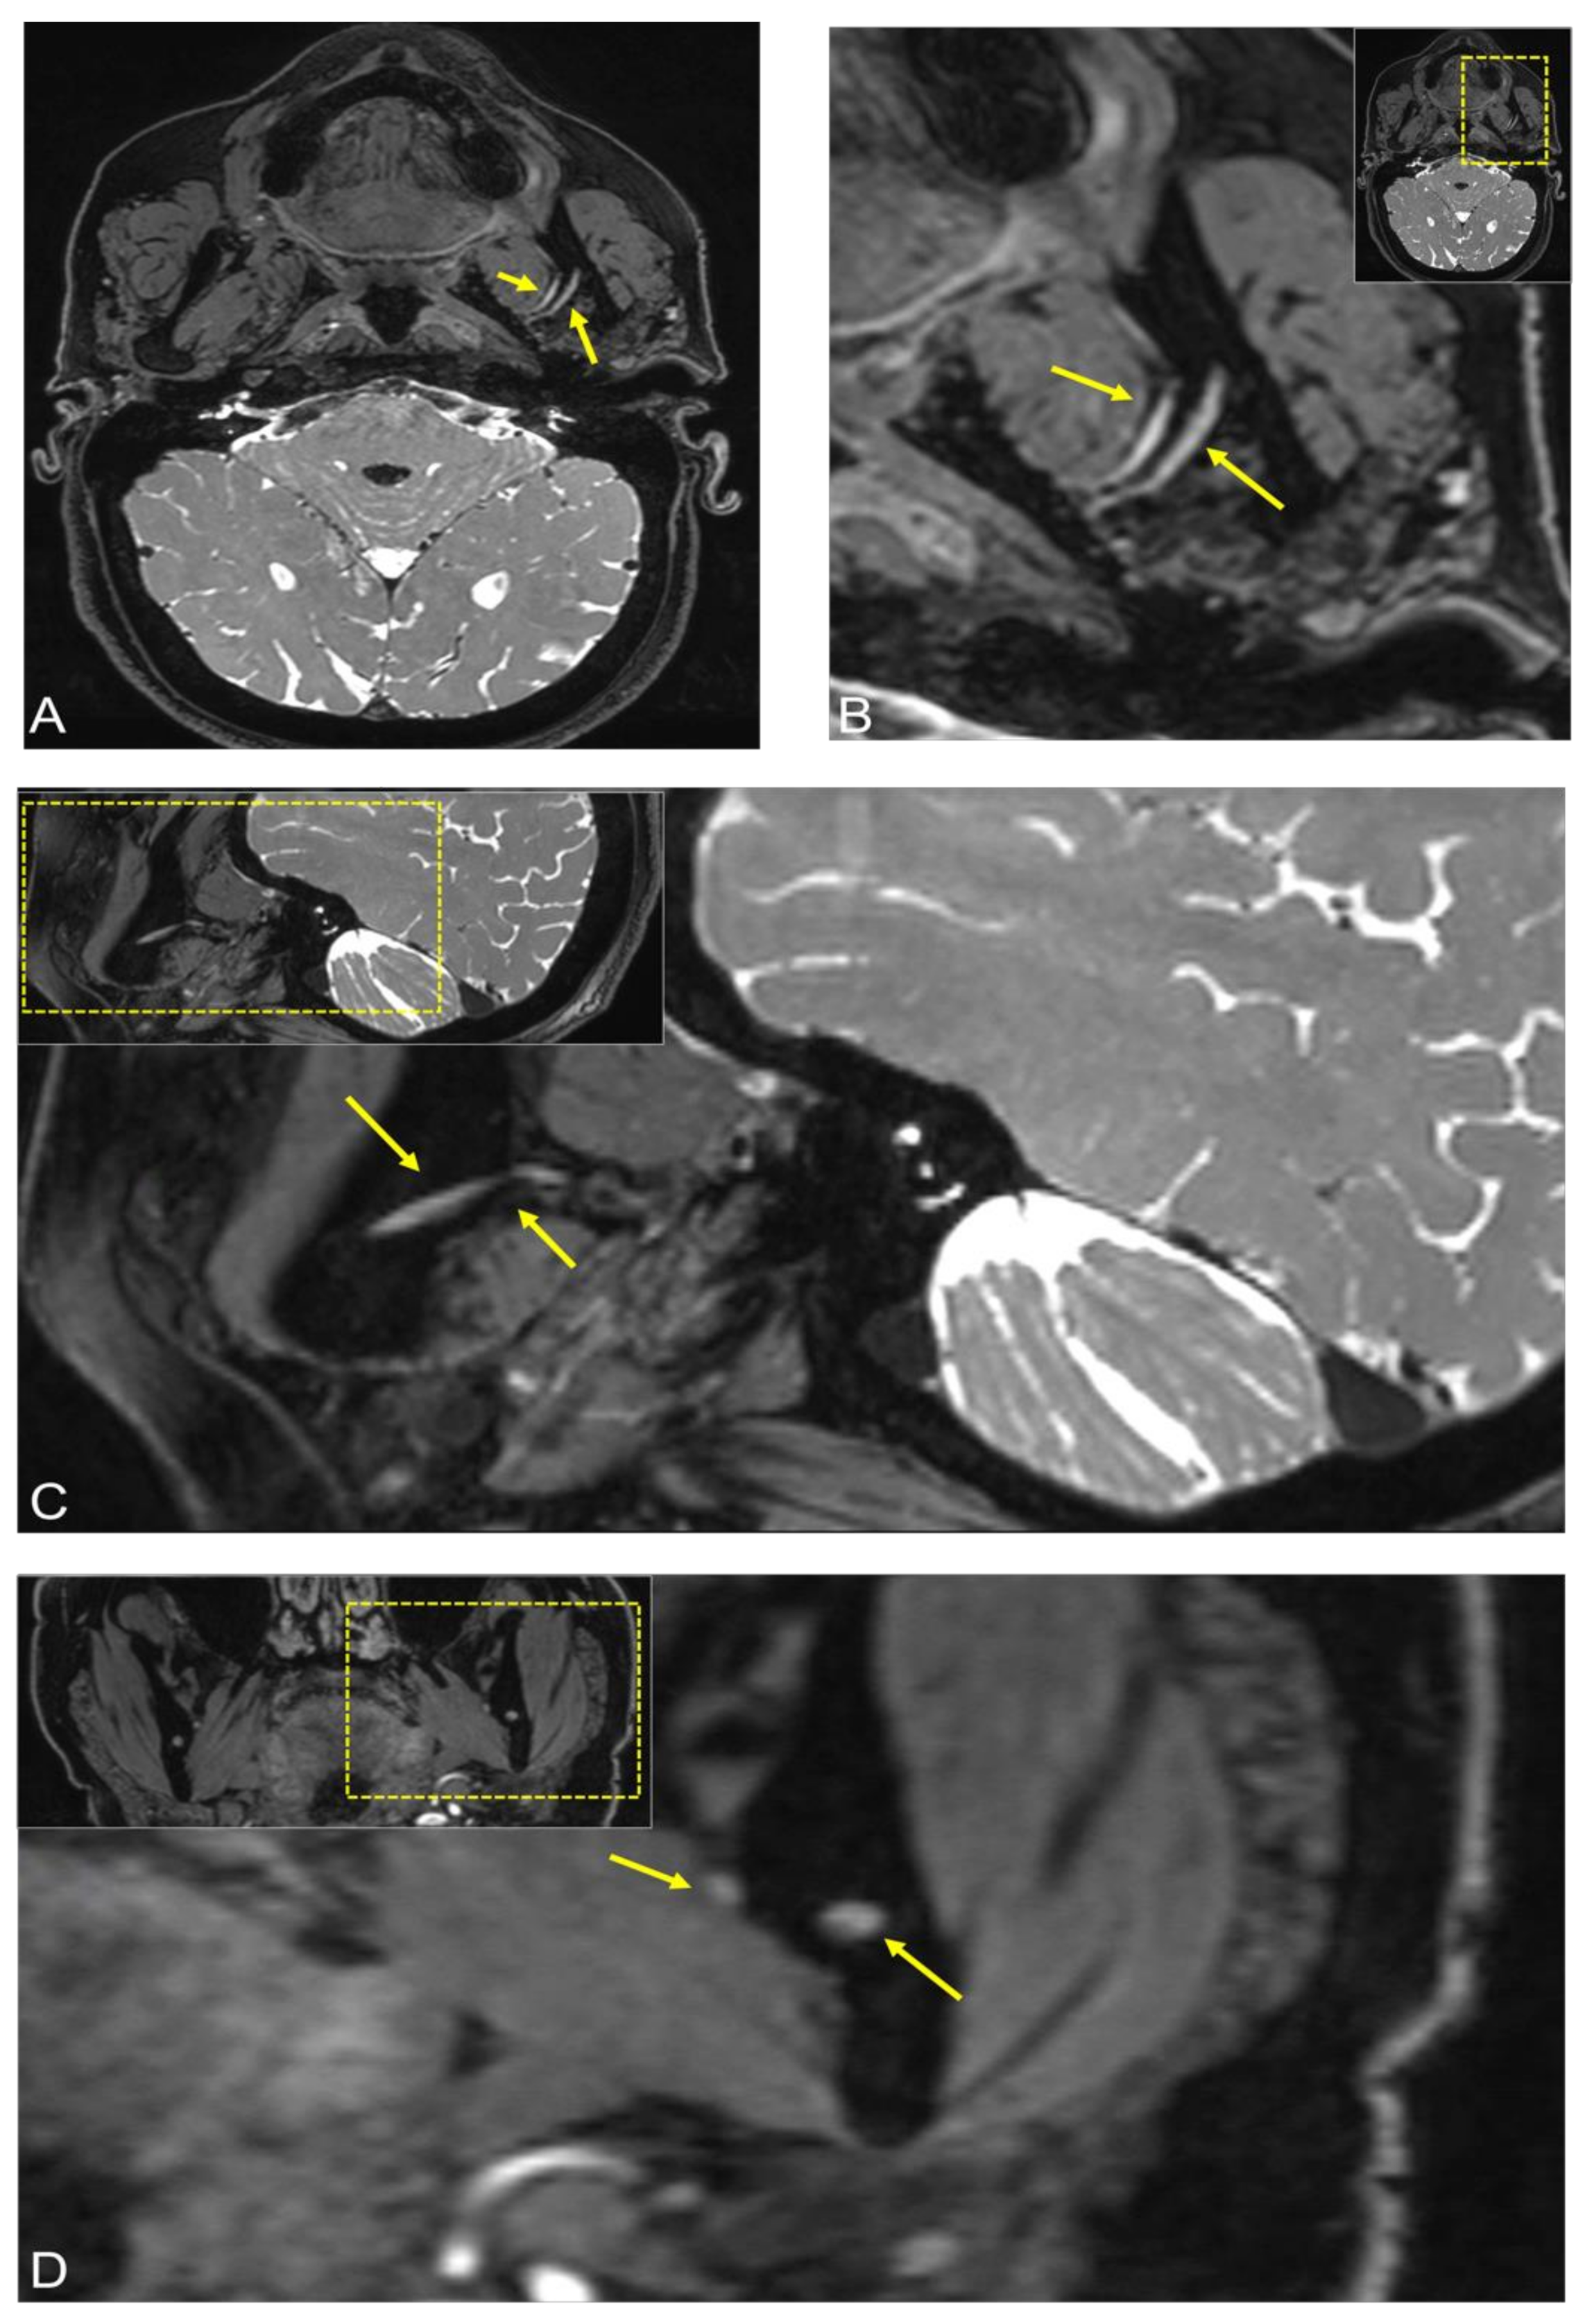

2.2. Case 2